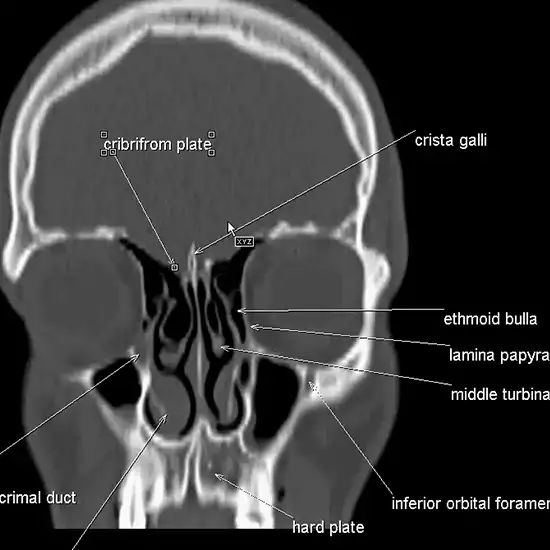

CECT (Contrast Enhanced Computed Tomography) Head and PNS(Para-Nasal Sinus) Axial is an imaging procedure that is used to create images of the head and PNS. For this scan, a Rotating X-ray beam and contrast media are used.

CECT PNS Axial detects the suspected diseases/ disorders of the sinus.